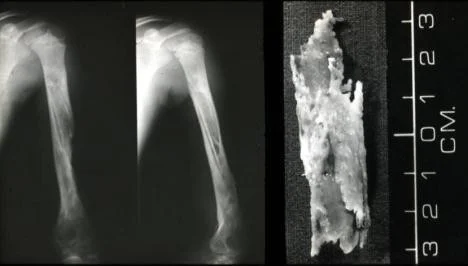

(A) Â An initial films reveals no abnormality

(B) A film taken 3 weeks later shows some destruction of the upper end of the tibia and an extensive periosteal reaction along the tibia, particularly the medial side (arrow).

(C) Bony sequestrum X-ray leg (left; AP view) of a child A fragment of bone has separated from adjacent bone and is surrounded by a lucent rim. chronic osteomyelitis.Â